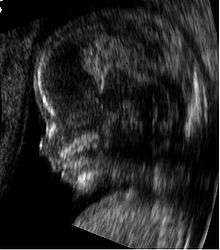

Ultrasound image of a fetus in the womb, viewed at 12 weeks of pregnancy (bidimensional-scan)

Human medicine

Medical sonography (ultrasonography) is an ultrasound-based diagnostic medical imaging technique used to visualize muscles, tendons, and many internal organs, to capture their size, structure and any pathological lesions with real time tomographic images. Ultrasound has been used by radiologists and sonographers to image the human body for at least 50 years and has become a widely used diagnostic tool. The technology is relatively inexpensive and portable, especially when compared with other techniques, such as magnetic resonance imaging (MRI) and computed tomography (CT). Ultrasound is also used to visualize fetuses during routine and emergency prenatal care. Such diagnostic applications used during pregnancy are referred to as obstetric sonography. As currently applied in the medical field, properly performed ultrasound poses no known risks to the patient.[23] Sonography does not use ionizing radiation, and the power levels used for imaging are too low to cause adverse heating or pressure effects in tissue. Although the long-term effects due to ultrasound exposure at diagnostic intensity are still unknown,[24] currently most doctors feel that the benefits to patients outweigh the risks.[25] The ALARA (As Low As Reasonably Achievable) principle has been advocated for an ultrasound examination – that is, keeping the scanning time and power settings as low as possible but consistent with diagnostic imaging – and that by that principle non-medical uses, which by definition are not necessary, are actively discouraged.[26]